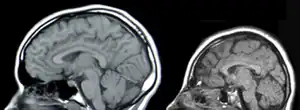

Microcefalia (do grego micrón, pequeno + céphalon, cabeça) é uma condição neurológica em que o tamanho da cabeça e/ou seu perímetro cefálico occipito-frontal (OFC) é dois ou mais desvios padrão abaixo da média para a idade e sexo.[1][2] Também é chamada de nanocefalia (do grego nánnos, e, on, "anão, muito pequeno" + kephalé, "cabeça").[3] Diferenciam-se diversas formas de manifestações clínicas e etiologias. A microcefalia verdadeira pode ser familiar e não necessariamente associada ao retardo mental.[4][5] Distingue-se das cranioestenoses e de anomalias específicas ou déficits do crescimento cerebral. Quer pelo pequeno tamanho da caixa craniana, quer pelo reduzido desenvolvimento do cérebro, é uma das causas de oligofrenia (défice intelectual).[6][7]

Fatores genéticos podem desempenhar um papel em causar alguns casos de microcefalia. Relacionamentos foram encontrados entre o autismo, duplicações de cromossomos e macrocefalia de um lado. Por outro lado, uma relação foi encontrada entre esquizofrenia, eliminações de cromossomos e microcefalia.[32][33][34] Além disso, foi estabelecida uma associação entre variantes genéticas comuns em genes de microcefalia conhecidos (MCPH1, CDK5RAP2) e variação normal na estrutura cerebral medida com imagens de ressonância magnética (MRI) - isto é, principalmente área de superfície cortical cerebral e total volume do cérebro.[35]